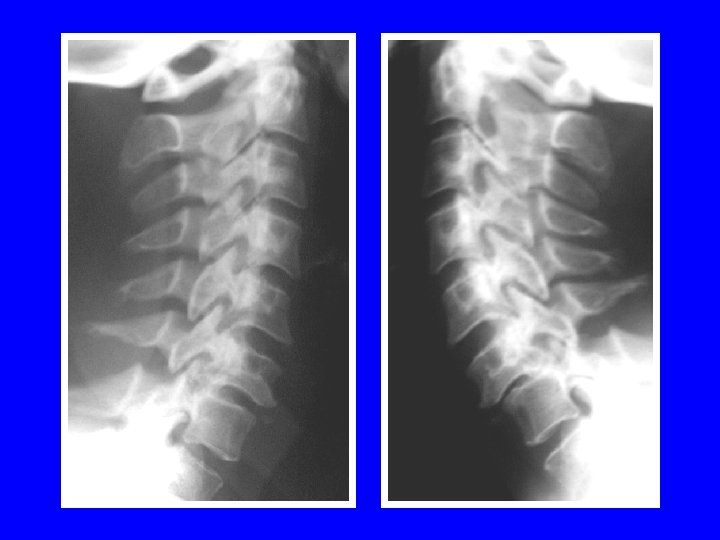

ENTORSE GRAVE DU RACHIS CERVICAL 1 baillement postérieur du disque 2 baillement interépineux 3 découverte articulaire sup > 1/3 4 CLICHES DYNAMIQUES

1 découverte articulaire supérieure 2 baillement interépineux 3 baillement postérieur du disque + découverte plateau supérieur

LUXATION PURE BILATERALE 41% de lésions médullaires pointes à pointes accrochage bilatéral

LUXATION UNILATERALE

24% atteintes médullaires 68% atteintes radiculaires